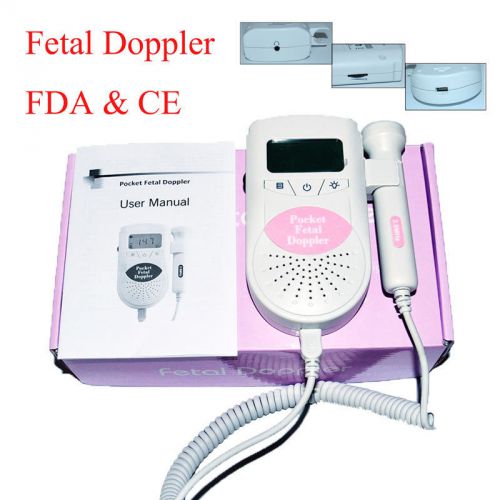

Hot Sale Ultrasound Fetal Prenatal Heart Rate Monitor Doppler 3MHz CE -Signals

LCD Pocket hand-held Ultrasound fetal doppler prenatal Baby heart beat monitor

Pink 3.0MHz Probe Ultrasound Prenatal Detector Fetal Doppler Baby Heart Monitor

LCD Prenatal Pocket Fetal Doppler Approved Baby Heart Beat Monitor Orange+Gel